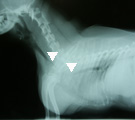

受診時。気管虚脱に対し気管内挿管の緊急処置が施されていた。 第1病日胸部X線写真。気管チューブを抜くと胸郭前口部で気管陰影消失(三角マーク間)。 引き続き、気管切開してシリコン製Tチューブを設置し気道確保した(マークはチューブ端を示す)。 第79病日、自己拡張型金属ステントに入れ替え、気管開存性と気道違和感が著明に改善した。